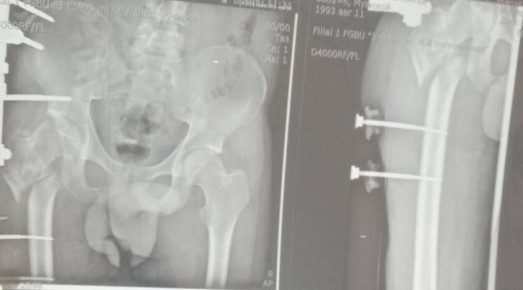

Уникальная операция в Луганской республиканской клинической больнице вернула ветерану специальной военной операции (СВО) возможность ходить без хромоты. Об этом сообщила министр здравоохранения ЛНР Наталия Пащенко. Руководитель Минздрава...

Об этом сообщила министр здравоохранения ЛНР Наталия Пащенко.Руководитель Минздрава рассказала, что борьба сержанта из ЛНР, мужчины 1993 года рождения, длилась три с половиной года. За это время он проходил лечение в десяти госпиталях, в том числе в...

Об этом сообщила министр здравоохранения ЛНР Наталия Пащенко в своем телеграм-канале.Боец ушел на фронт 25 февраля 2022 года, прошел через горнило Херсонщины, а тяжелое ранение получил 28 августа.«Из-за обширных повреждений и многократных операций...

Об этом сообщила министр здравоохранения ЛНР Наталия Пащенко.Боец ушел на фронт 25 февраля 2022 года, прошел через горнило Херсонщины, а тяжелое ранение получил 28 августа.«Три с половиной года борьбы. Десять госпиталей. И одна операция, которая...